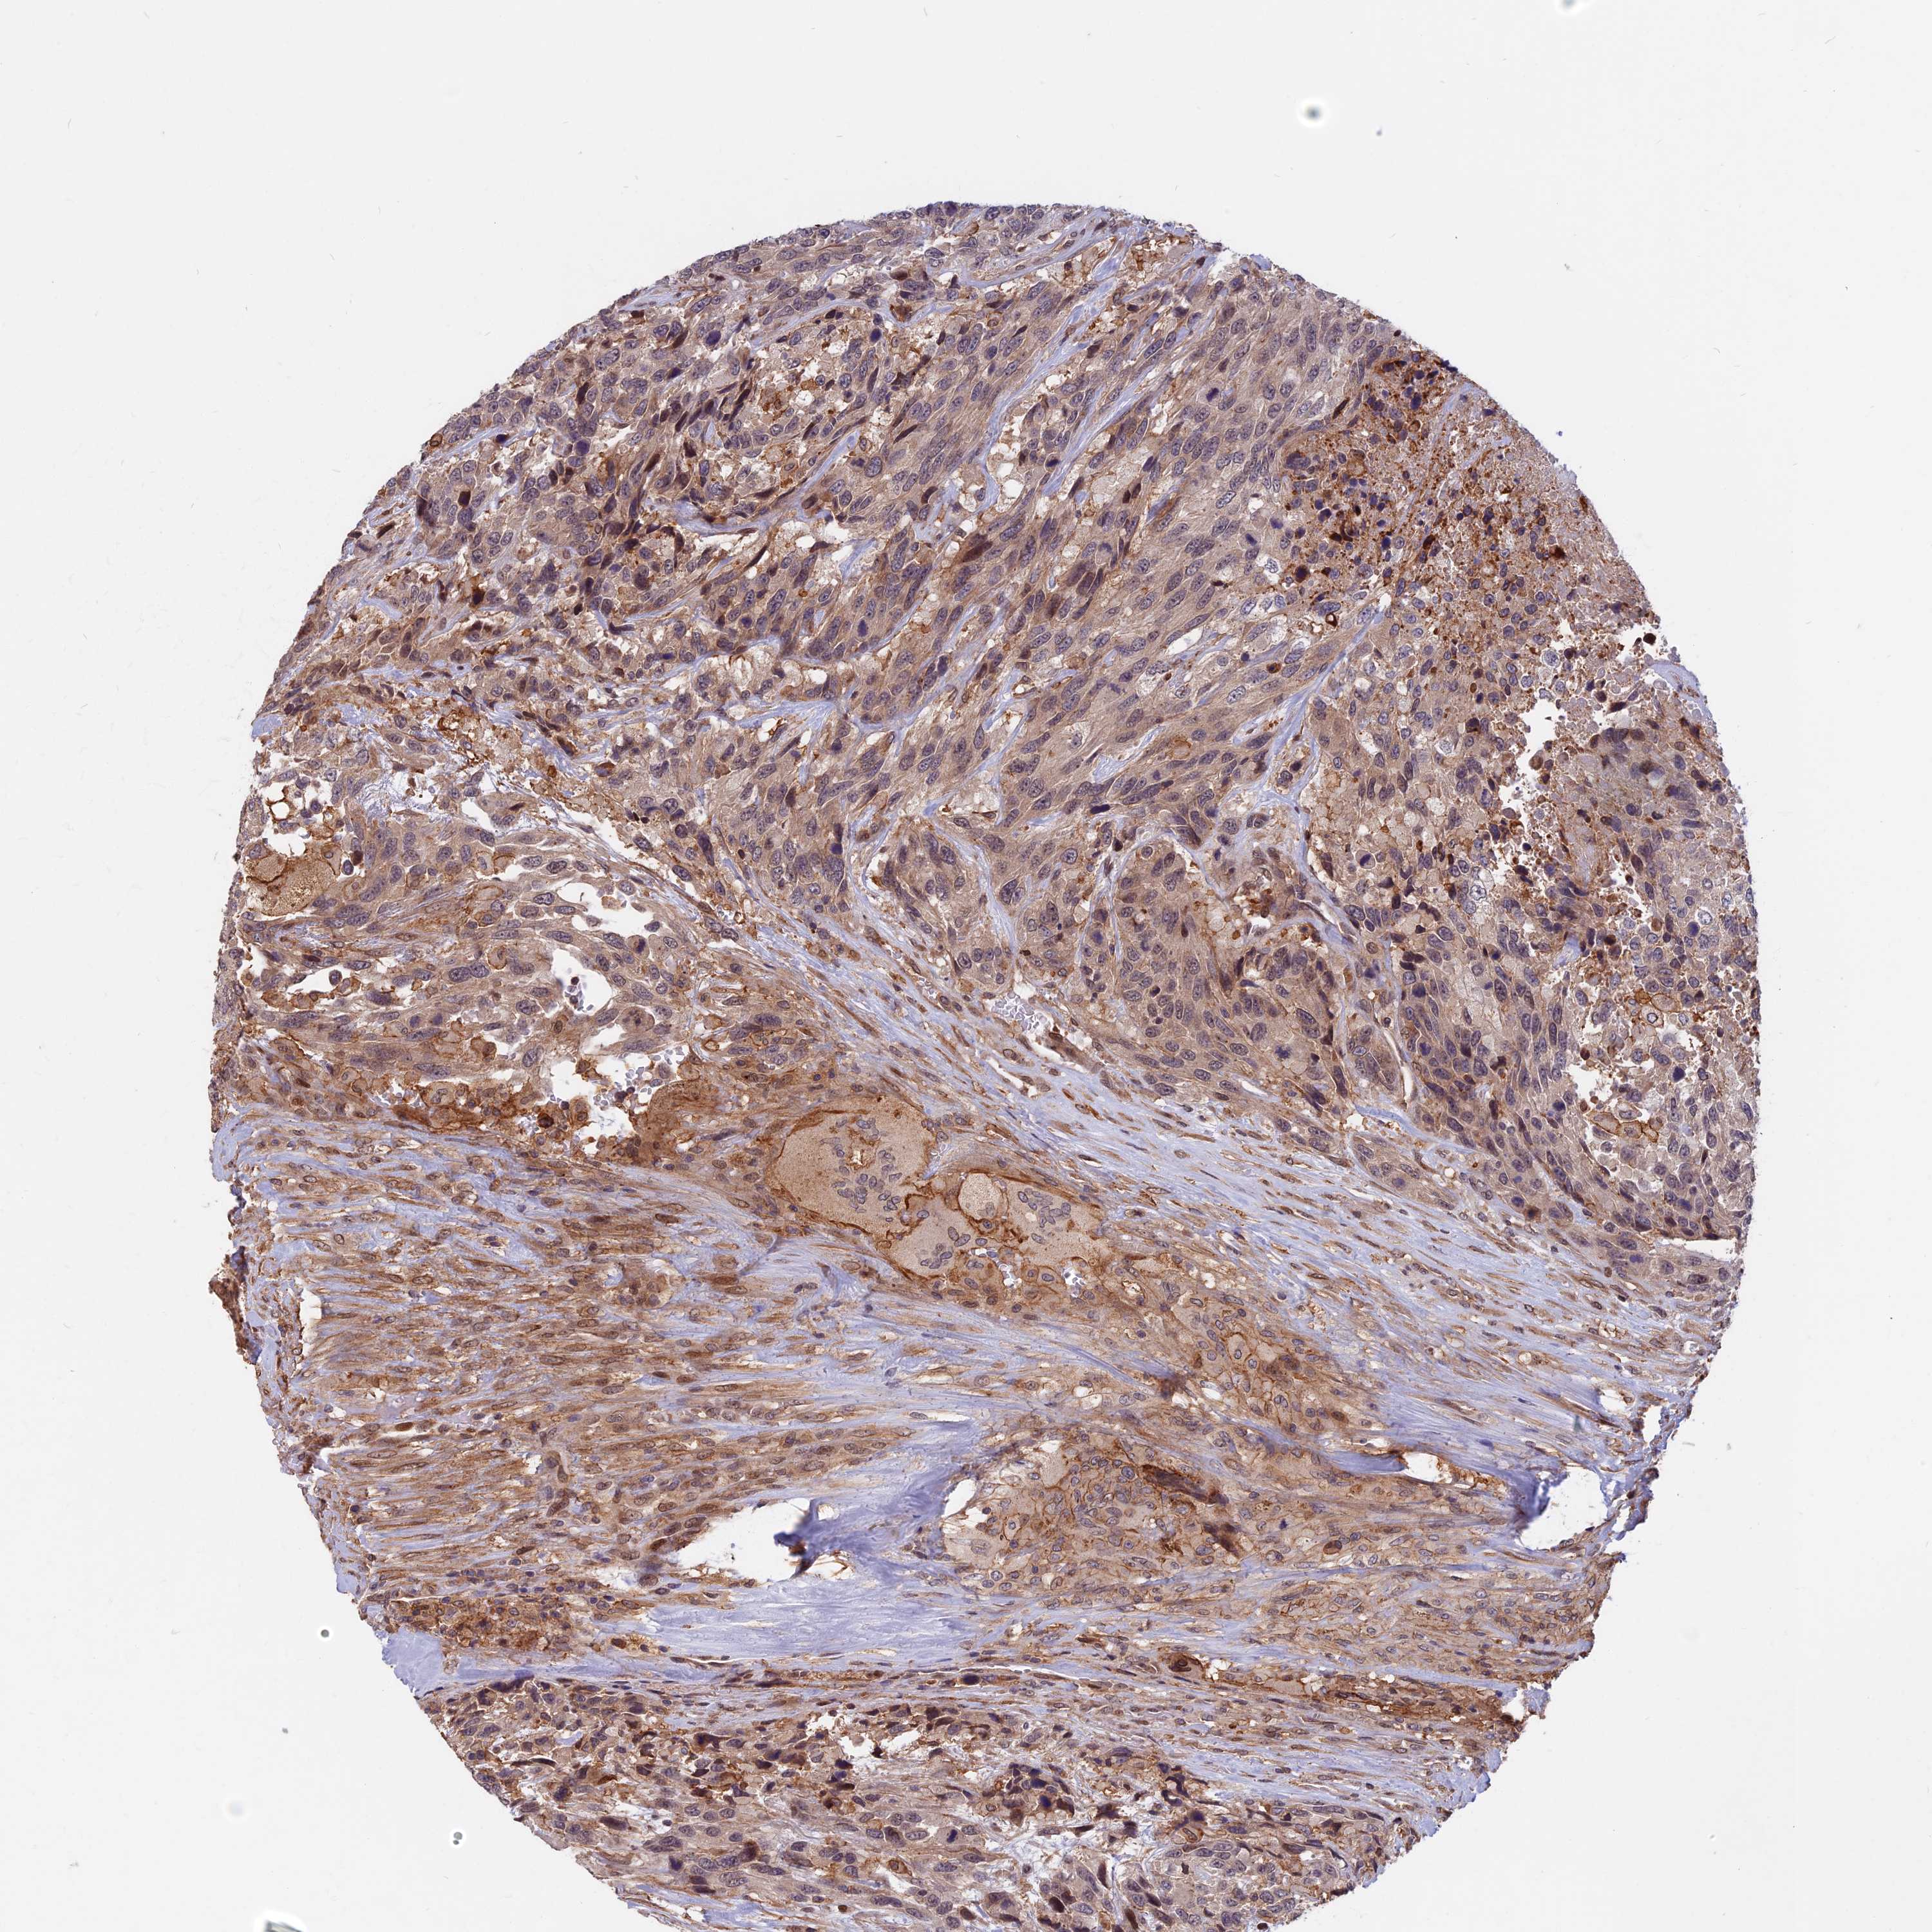

UROTHELIAL CANCER - Protein expressioni

A mouse-over function shows sample information and annotation data. Click on an image to view it in a full screen mode. Samples can be filtered based on level of antibody staining by selecting one or several of the following categories: high, medium, low and not detected. The assay and annotation is described here.

Antibody stainingi

Antibody staining in the annotated cell types in the current human tissue is reported as not detected, low, medium, or high, based on conventional immunohistochemistry profiling in selected tissues. This score is based on the combination of the staining intensity and fraction of stained cells.

Each image is clickable and will lead to virtual microscopy that enables deeper exploration of all samples and also displays staining intensity scores, fraction scores and subcellular localization as well as patient and tissue information for each sample.

Antibody HPA040412

Antibody HPA040947

Staining

High

Medium

Low

Not detected

Intensity

Strong

Moderate

Weak

Negative

Quantity

>75%

75%-25%

<25%

None

Location

Nuclear

Cytoplasmic/membranous

Cytoplasmic/membranous,nuclear

Urothelial carcinoma, High grade